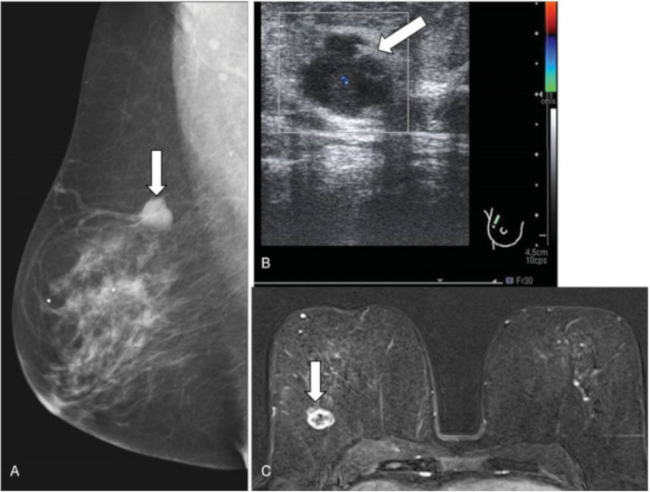

Las lesiones papilares de la mama (► Fig. 1) son proliferaciones arborescentes del epitelio ductal, con un pedículo fibrovascular. Se desarrollan en la luz adheridas a las paredes en cualquier parte del sistema ductal, desde el pezón hasta la unidad ducto-lobulillar más periférica. Representan menos de un 3% de las lesiones mamarias sólidas y pueden ser solitarias o múltiples. Según su clasificación histológica se dividen en benignas, atípicas y malignas; incluyendo dentro de esa última, al carcinoma intraductal y al carcinoma papilar invasor.

Papilomatosis florida. Mujer de 52 años, que acudió a consulta por induración en mama izquierda. (A) Mamografía digital. Asimetría focal con mayor densidad en cuadrante superior externo (CSE) de mama izquierda (puntas de flecha). (B) Ecografía. Nódulo hipoecoico de morfología irregular (flecha). (C) Resonancia magnética (RM) con contraste intravenoso. Realce de contraste en CSE de mama izquierda, no masa, de distribución regional (círculo). El resultado histológico tras biopsia con aguja gruesa (BAG) fue de papilomas múltiples. Se realizó una extirpación quirúrgica, con resultado final de papilomatosis florida con hiperplasia ductal atípica.